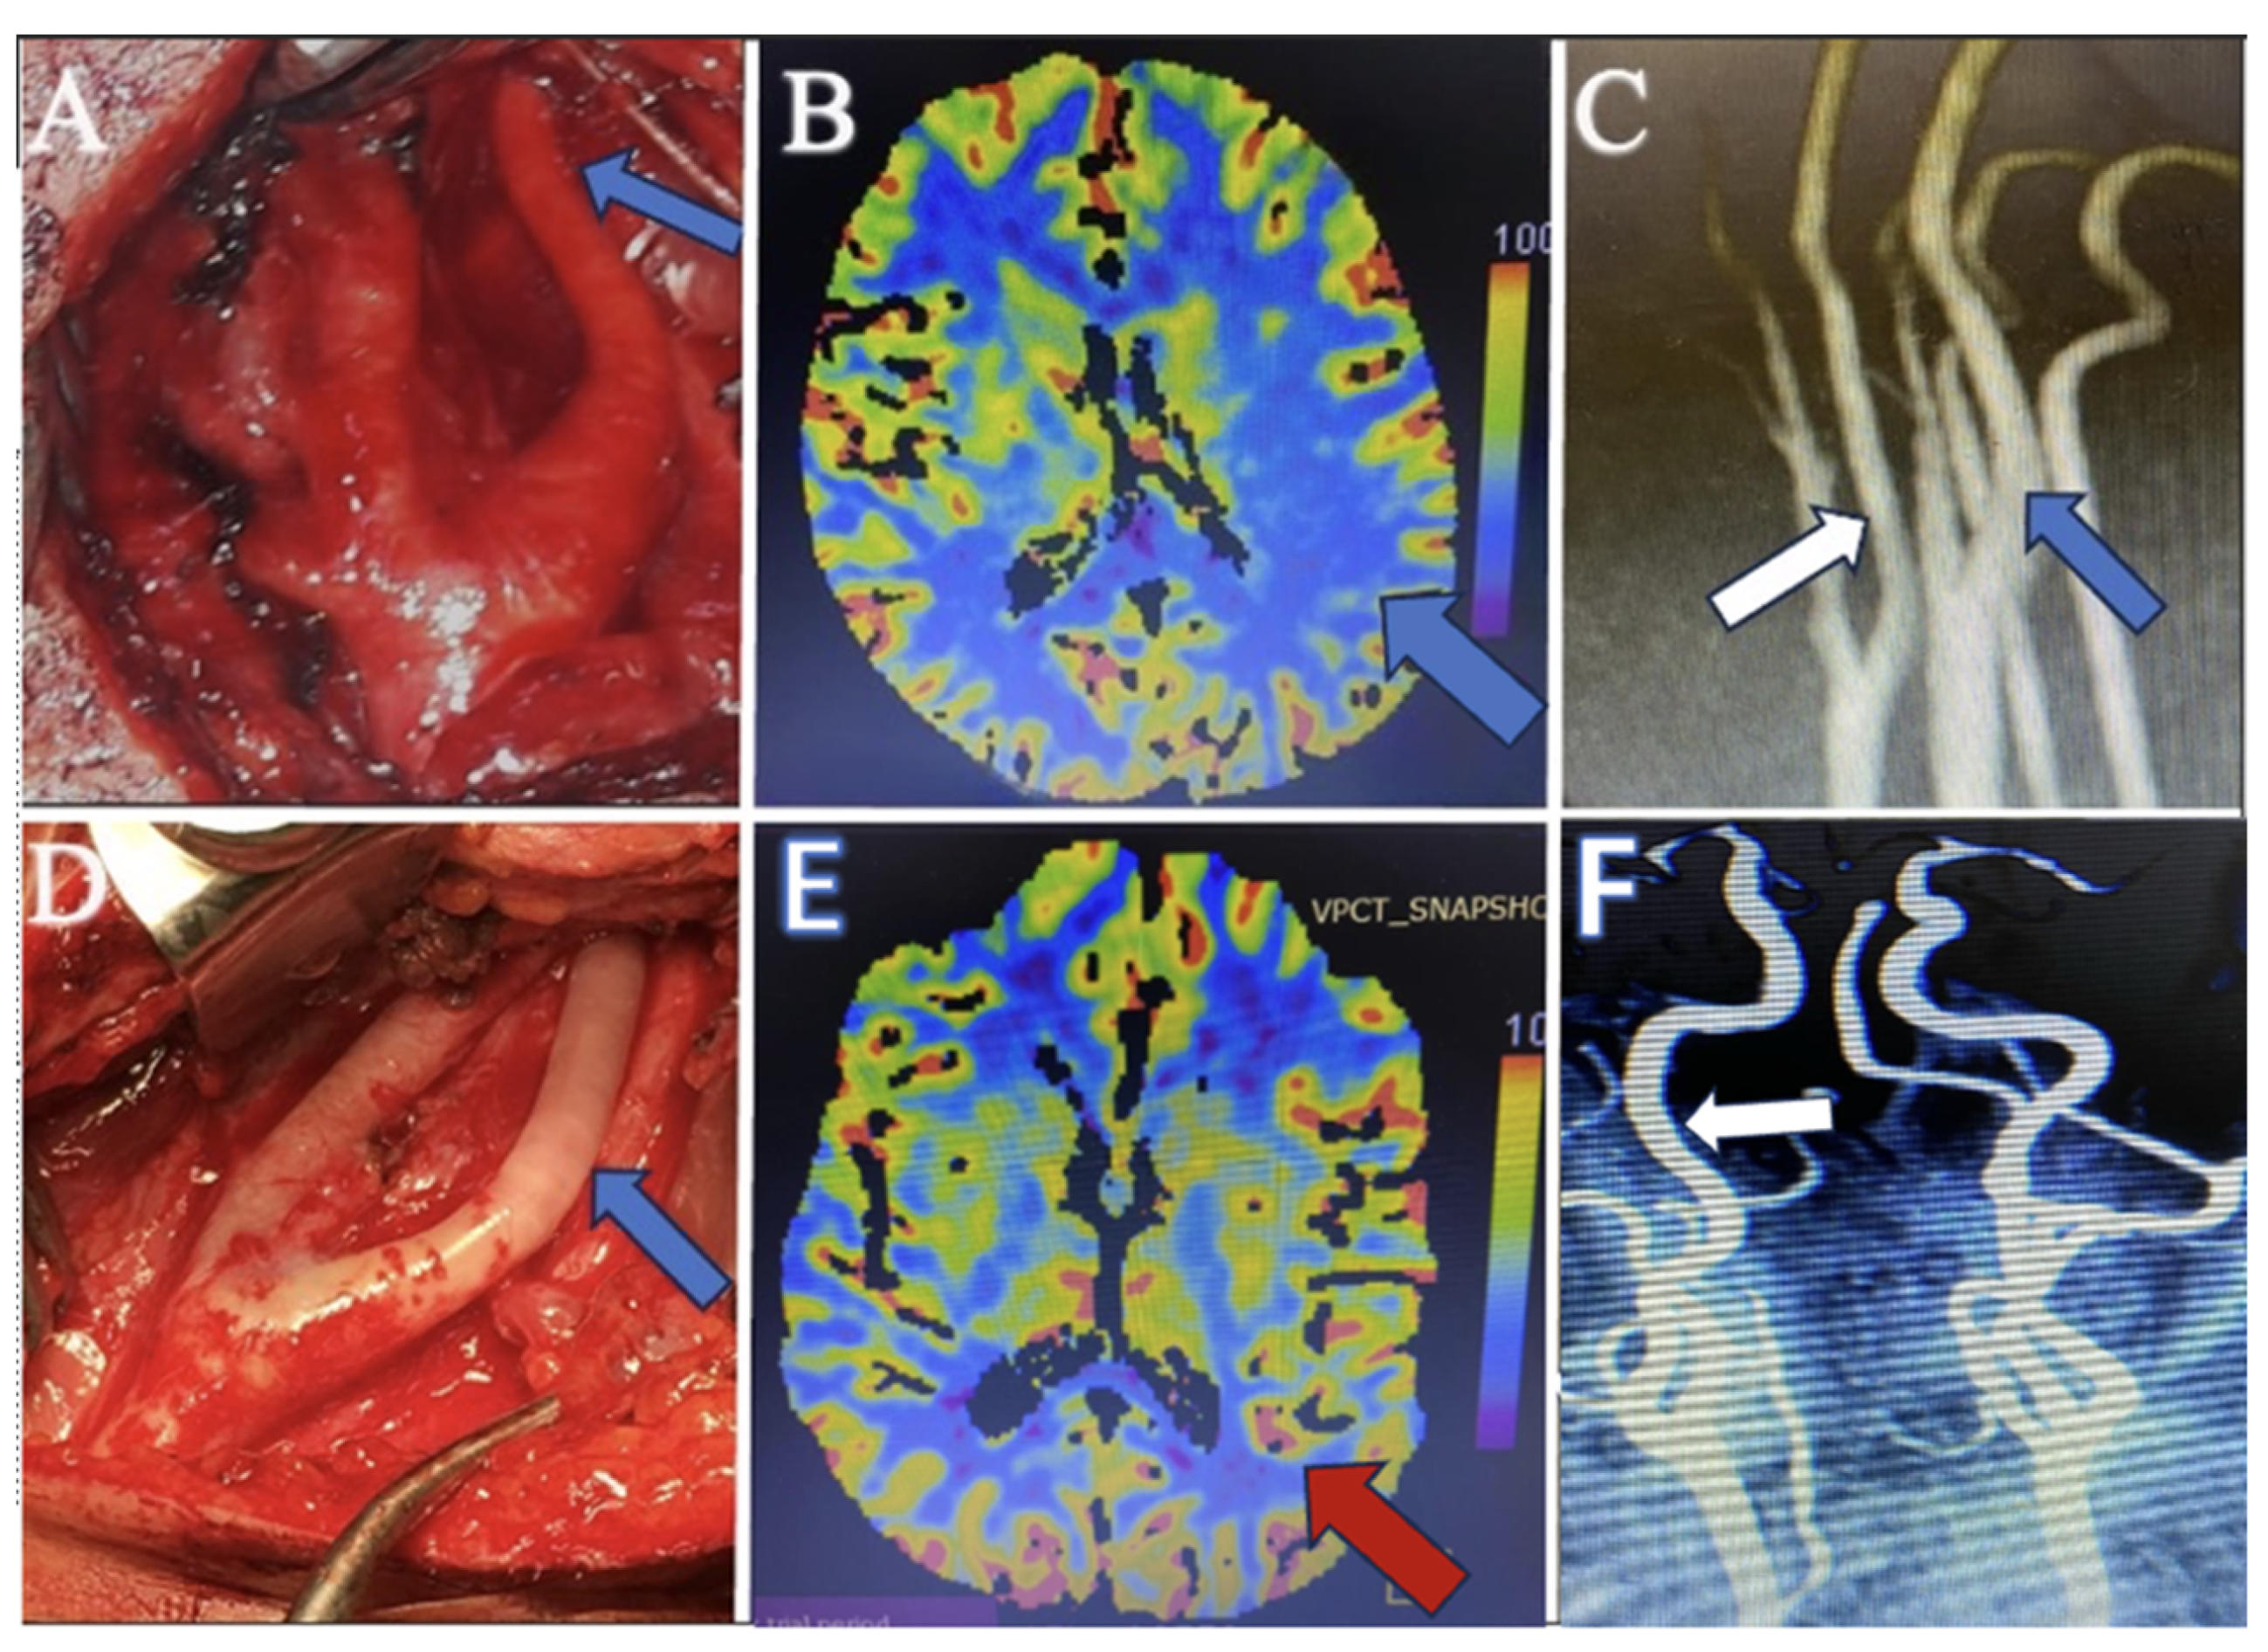

Hemiparesis, observed in conjunction with other conditions, improved significantly in all patients postoperatively. This reinforces the importance of adequate cerebral perfusion and the role of ICA tubular stenosis in cerebral ischemic events. While recognized, the link between stenosis and motor deficits has been underscored by our findings, which demonstrate marked postoperative neurological recovery. In our study, patients with hemiparesis associated with migraines and TIAs underwent perfusion images. In eight of the ten affected patients, areas of hypoperfusion that could contribute to these symptoms were identified despite the lack of findings in standard MRI scans. This suggests that perfusion imaging can reveal cerebral blood flow deficits not apparent in conventional MR images pre- and postoperatively, as depicted in Figure 3.

During the surgical exploration for managing carotid artery stenosis, an abnormal observation was made concerning the relative calibers of the carotid vessels. When evaluating MR angiographies, it is essential to compare the ICA with the ECA on the same side and the ICA on the opposing side to ensure that long-segment tubular stenosis is not missed. In cases where MR angiography reveals similar calibers between the ICA and ECA, surgical findings demonstrate a notably narrower ICA than the ECA, and a detailed assessment, including clinical presentation and additional MR modalities, such as perfusion studies, becomes crucial. This comprehensive approach is necessary to establish a diagnosis of tubular stenosis, especially when imaging findings may not fully correlate with intraoperative observations, as depicted in Figure 3. Therefore, heightened vigilance is imperative to ensure that such pathologies are noticed.

Figure 3. (A) Perioperative surgical microscope view before intervention demonstrates the long-segment tubular stenosis of the internal carotid artery (blue arrow). (B) Preoperative perfusion CT image shows the hypoperfusion area in the paracentral lobule (blue arrow), which explains the patient’s TIA attacks and hemiparesis. (C) The preoperative MR angiography image shows the internal carotid artery (white arrow) having a similar diameter to the external carotid artery. However, it appears narrower than the internal carotid artery on the opposite side (blue arrow). (D) Perioperative surgical microscope view after perivascular sympathectomy, which shows the dilatation of the internal carotid artery (blue arrow). (E) Postoperative perfusion CT images demonstrate the perfusion restoration (red arrow), which is compatible with postoperative improvement. (F) Postoperative MR angiography shows the dilatation of the internal carotid artery (white arrow).